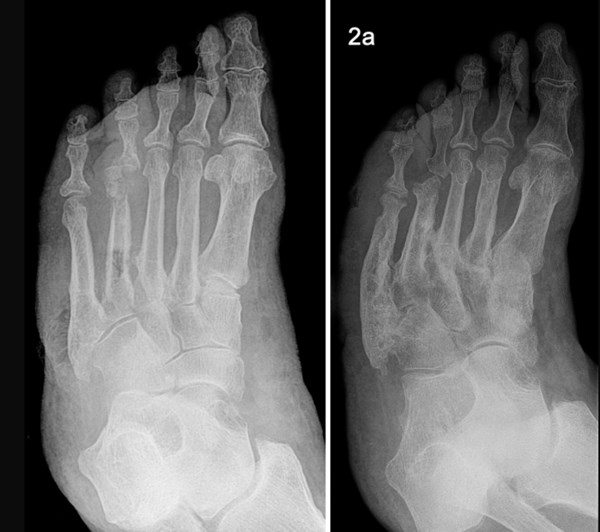

• Plain X-ray:  Useful to determine location - the most commonly affected joints in Charcot arthropathy are in the midfoot region (ie, the cuneiform/metatarsal area) [12] (Figure 22 and 23).

Figure 22: Charcot foot. X-rays of the same foot, showing progression of disease over 2 years. Fractures in the cuneiform/metatarsal area [120].